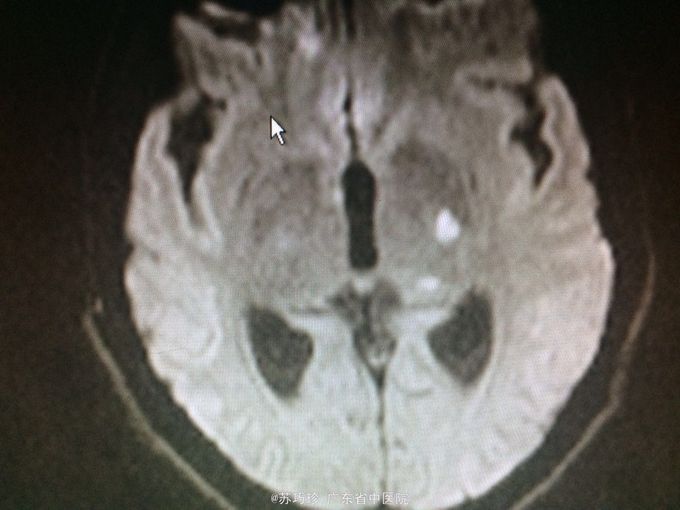

查体:心肺腹(-)。视物重影,右眼外展不到位,T8以下痛、触觉减退,右上肢肌力4级,双下肢肌力0-1级,双下肢肌张力降低,双下肢腱反射消失,腹壁反射消失,颈抵抗约3横指,克氏征(+)。 辅助检查:血常规、肝肾功能及心电图、腹部B超检查未见异常。胸部CT+增强:左肺上叶下舌段慢性炎症;双侧少量胸腔积液,双肺下叶含气不全。头颅+胸椎+腰椎MR平扫+增强:双侧额顶颞枕叶脑沟、双侧侧脑室室管膜、双侧小脑半球软脑膜、脑干软脑膜、颈胸腰段脊髓软脑膜、马尾异常强化影,结合临床考虑炎症性病变;左侧颞叶、左侧丘脑、左侧内囊后肢异常弥散,提示急性脑梗塞灶与感染灶相鉴别,建议复查;脑室系统改变,考虑脑积水;T7/8椎间盘变性,邻近椎体许莫氏结节形成;胸腰椎骨质信号未见异常;骶管囊肿。心脏彩超:EF:64%,主动脉瓣少量返流,左室顺应性减退,少量心包积液。